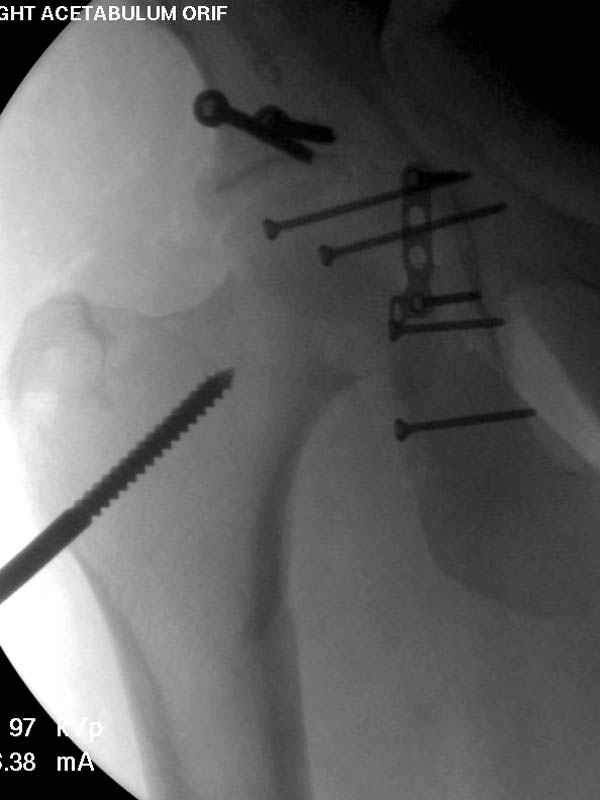

По снимку создается впечатление о высоком поперечном переломе, задней колонны, стенки; почему не пользовались *magic screw*?

Латеральное положение облегчает проведение тракции через вертел, за 5 мм стержень за вертел (грузом через тракционное приспособление), на обычном рентгенопрозрачном операционном столе, а для положения на животе, наверное, Judet Table более приемлем, потому что там имеется латеральное тракционное устроиство.

Там множество обычных 2.7 мм шурупов, потом идет фиксация основными пластинами.

Полную нагрузку разрешаем в 12 недели, хотя движения в суставе с первых дней.

Снимки здесь....